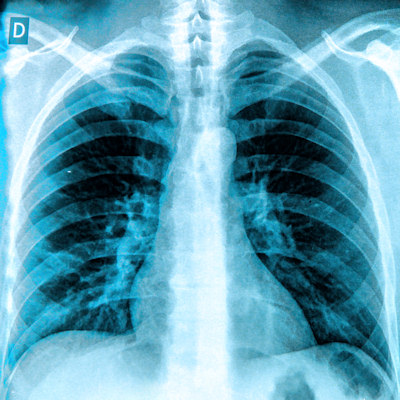

London-based medical AI company Bering Limited has received U.S. Food and Drug Administration (FDA) 510(k) clearance for its BraveCX AI-powered chest x-ray triage software.

BraveCX is a computer-assisted triage and notification software that analyzes adult (≥ 18 years old) chest x-rays for the presence of prespecified suspected findings. The product was developed on over 1 million chest x-rays and has yielded an area under the curve of 0.96 for pleural effusion and 0.98 for pneumothorax in testing, the company said.